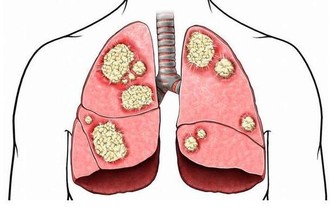

夏天毒素如果無法排出體外,就會向內滲透,血液毒素垃圾過多就會形成血栓,所以在夏季得心腦血管疾病的人也會很多,因此在夏季最熱的三伏天我們也要注意排血毒。

Α-亞麻酸是排血毒,清除血液垃圾,維持血管健康的重要物質,充足的α-亞麻酸可以幫助我們減少血管壁斑塊殘留,維持血管暢通,對預防心腦血管疾病有益。蘇子油和胡麻仁油等植物油都是富含α-亞麻酸,可以每天食用5ml。